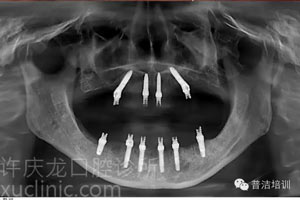

然而,冰凍三尺非一日之寒。患者無牙的原因大部分是長期缺乏牙科保健的結(jié)果。而且無牙患者常常伴有嚴(yán)重的牙骨萎縮。這無疑增加了種植修復(fù)的難度。患者在承受各種手術(shù)痛苦的同時(shí)還要負(fù)擔(dān)高額的費(fèi)用。

![]() | ![]() | |

植牙前口內(nèi)照 | 植牙前CT圖 |